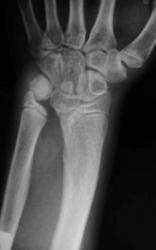

Девочка 14 лет. Ранее за помощью не обращались. Только в этом возрасте родителей и саму пациентку начала беспокоить деформация предплечий.

Рентгенологическая классика для болезни Маделунга:

1. Укорочение лучевой кости.

2. «Скошенность» суставной поверхности дистального эпифиза лучевой кости в ладонную и локтевую сторону, что «симулирует» визуально подвывих костей запястья.

3. «Нависание» полулунной кости над ладонным краем дистального эпифиза лучевой кости.

4. Высота дистального эпифиза по лучевой стороне превосходит его высоту по локтевой стороне.

5. В результате раннего закрытия ростковой зоны по локтевой и ладонной стороне, формируется ладонный и локтевой наклон суставной поверхности.

6. Деформация и изменение расположения проксимального ряда костей запястья, по форме, напоминающей «клин», вершиной которого является полулунная кость.

7. Головка локтевой кости находится в положении «вывиха» и смещена в «тыльном» направлении, по отношению к лучезапястному суставу.